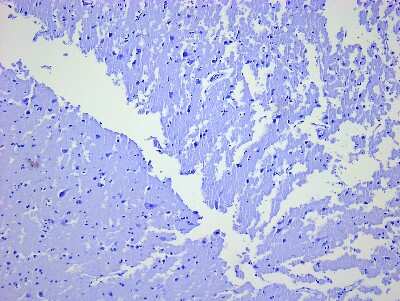

8 results for "Brain Postcentral Gyrus Slides and MicroArrays" in Products

Brain Postcentral Gyrus: Slides and MicroArrays